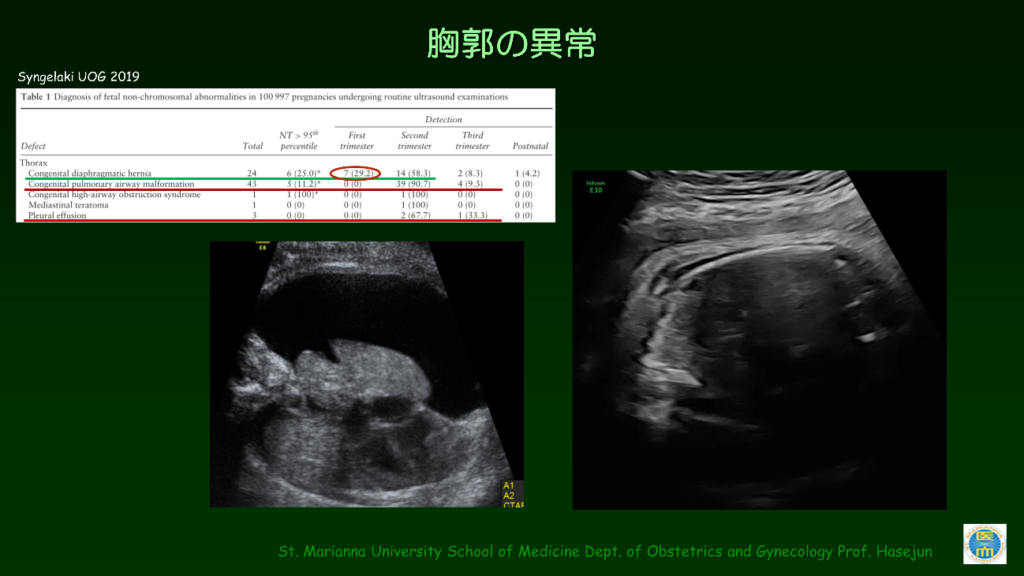

FMFについて(出生前診断)|おおのたウィメンズクリニック埼玉。インターネットホスピタル。胎児超音波診断ファントム “SPACE FAN-ST” | 京都科学。山形県庄内産 つや姫 白米5kg Gセレクション 特別栽培米。裁断済み。書き込みありです。了承の上ご購入検討ください。「胎児超音波診断」松田 義雄 / 谷垣 伸治定価: ¥ 8500#松田義雄 #松田_義雄 #谷垣伸治 #谷垣_伸治 #本 #自然/医療・薬学・健康。超音波外来|綱島クリニック|横浜市港北区の内科、婦人科、産科。。プロメテウス解剖学第三版